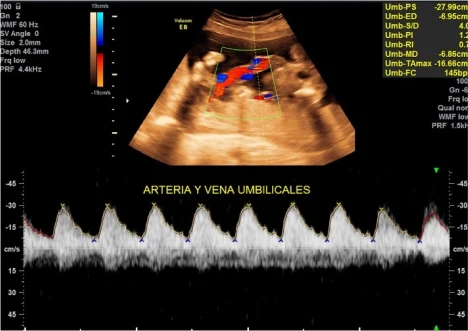

Doppler de Embarazo

11-13+6 / 22-24 / 30-34 Semanas

Para qué sirve la Ecografía Doppler

Sirve para medir flujos internos de las arterias uterinas y con ello medir riesgos hipertensivos en la madre, además de buscar en ciertas semanas marcadores de riesgos cromosómicos como síndrome de down, turner, etc.